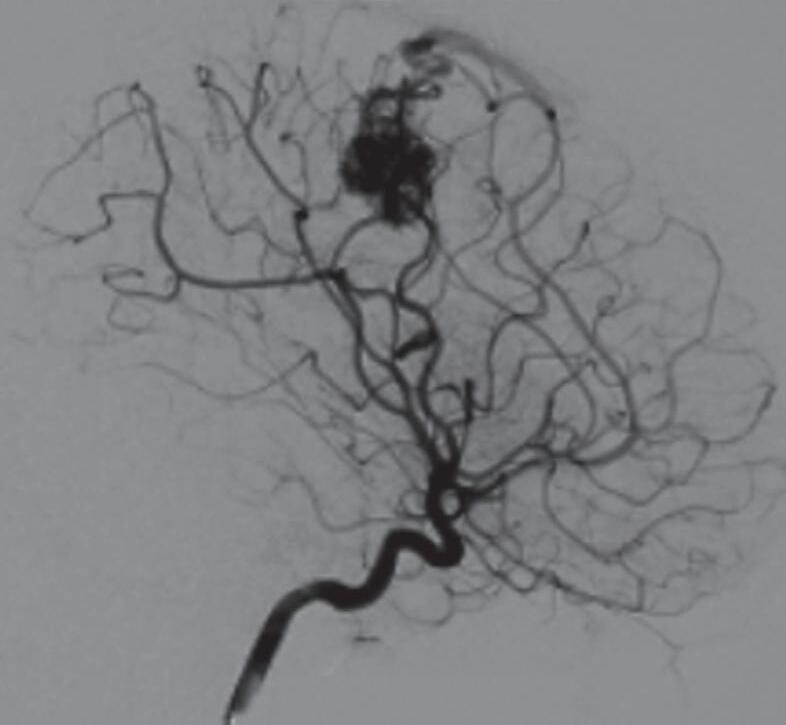

Fig. 1-8. (a-c) RNM T1 com contraste, cortes sagital (a), coronal (b) e axial (c) demonstrando MAV não rota com nidus localizado no lobo occipital à esquerda (setas longas). (d) Arteriografia digital cerebral com injeção de contraste via carótida direita (AP) mostrando a contribuição da carótida direita na irrigação da MAV contralateral. (e,f) Com injeção de contraste via carótida esquerda, em Perfil e AP respectivamente, observa-se nidus compacto nutrido por ramos da artéria cerebral média à esquerda e a veia de drenagem precoce se dirigindo para o seio sagital superior. Projeções em AP (g) e em perfil (h) demonstrando a contribuição do sistema vertebrobasilar por meio de ramos distais da artéria cerebral posterior à esquerda e drenagem para os seios sagital superior e sigmoide à esquerda (setas curtas).